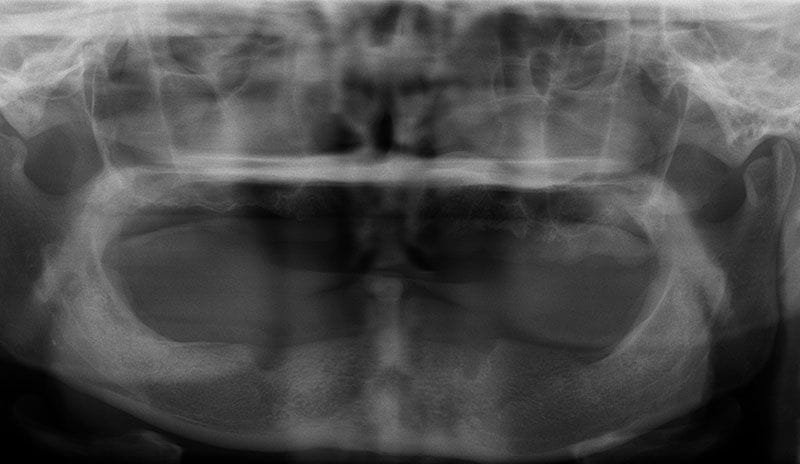

許多人缺牙多年後才想要植牙,但此時齒槽骨已萎縮,少了堅固的骨頭做為牙根的支撐當然不會穩固。因此可以把補骨想成幫牙根打地基,有了堅硬的地基再植入人工牙根,植牙效果才會穩定耐用。